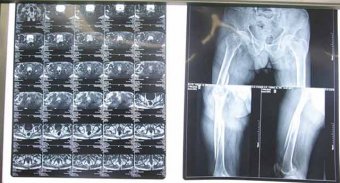

潘先生,男,71歲,五個月前騎自行車時不慎摔倒,傷及左髖部,傷后即感左臀部壓痛,左下肢短縮,活動受阻。來到濰坊市市立醫(yī)院骨科門診。 脊椎微創(chuàng)科主任、副主任醫(yī)師孫守全為患者進行...